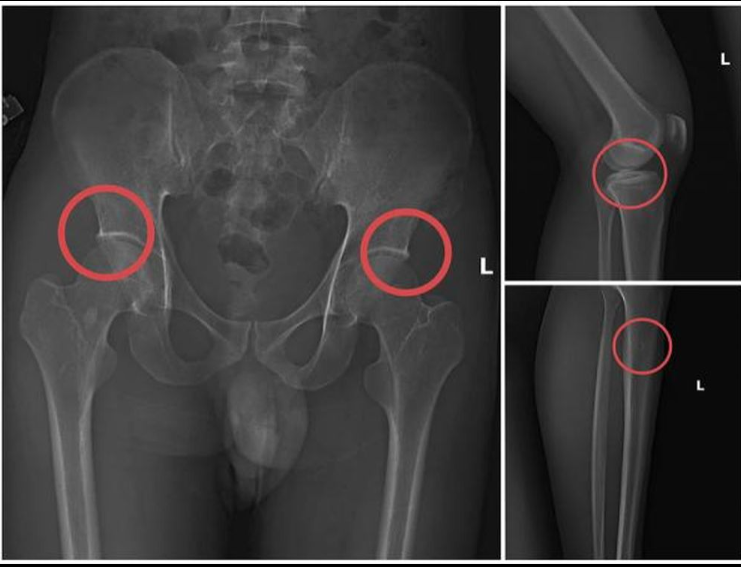

Phim chụp XQ một số tổn thương xương do đối tượng Tạ Minh Châu tạo ra.

Quá trình đấu tranh, Công an làm rõ Châu từng làm cộng tác viên cho Công ty bảo hiểm MB, biết rõ loại thương tích nào được chi trả cao nhất. Cộng với kiến thức về giải phẫu xương sau 6 năm làm việc tại khoa chẩn đoán hình ảnh, Châu nắm rõ vị trí và kỹ thuật để tạo ra vết nứt, vỡ xương có hình ảnh X-quang giống tai nạn thật.

Tại đây, Châu trực tiếp tiêm thuốc mê vào tĩnh mạch, đợi nạn nhân bất tỉnh rồi dùng búa và kim tiêm lớn đục mạnh vào xương, thường là xương chậu hoặc xương đùi - những vị trí có mức chi trả cao nhất. Sau khoảng 10-20 phút, khi thuốc mê hết tác dụng, nạn nhân tỉnh lại và được Châu hướng dẫn dựng hiện trường tai nạn giả như ngã suối, bị điện giật rồi nhập viện để lấy bệnh án hợp thức hóa hồ sơ yêu cầu bảo hiểm.